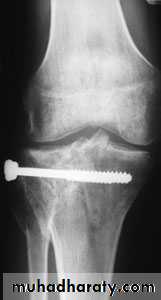

Tibial plateau fractures:Direct blow or fall from height may cause fracture of one tibial condyle or both.

Fracture lateral condyle is the commonest named as bumper fracture

caused by a force that abducts the tibia upon femur while the foot is fixed on ground.Patient usually is an adult, the knee joint is swollen, bruises, there is diffuse tenderness and doughy feel of haemarthrosis.

ligaments injuries must be excluded.

Imaging : X-ray

: anteroposterior, lateral & oblique views.

CT -Scan may used to detect amount of depression and comminuation.Tibial plateau fracture

Treatment:

Undisplaced fractures

treated conservatively:Haemarthrosis aspiration and compression bandaging,

above knee cast for one monthsfollowed by functional brace and physiotherapy.

For displaced fracturestreatment is by open reduction and internal fixation with

plate and screws as it is an intra articular fracture.fixation of tibial plateau fracture